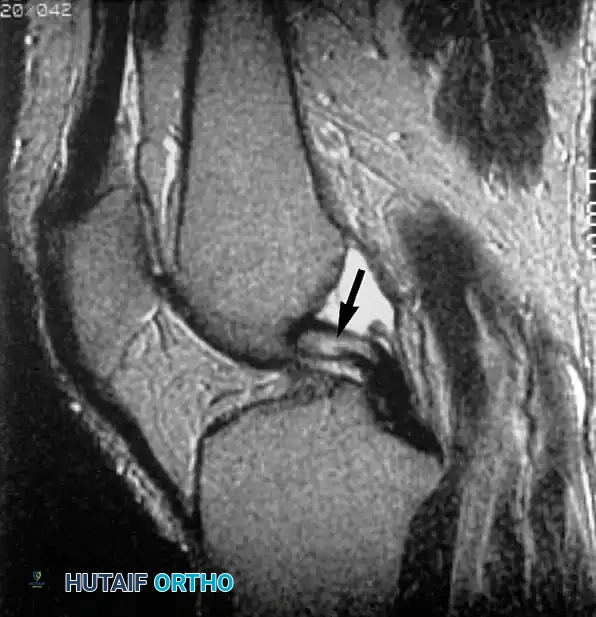

التمزقات المعقدة والمزاحة

بعض التمزقات تكون شديدة لدرجة أن جزءا من الغضروف ينفصل وينزاح من مكانه الأصلي ليستقر في منتصف المفصل، مثل تمزق يد الدلو، مما يسبب انغلاق الركبة الميكانيكي.

في حالات أخرى، قد ينزاح الجزء الممزق إلى الأسفل تحت الأربطة الجانبية.